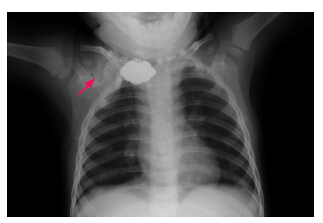

患儿男,1岁,因发现右肩部肿物1周就诊。1周前发现右肩肿物,约小核桃大小,无外伤史。体查:右肩中部皮下可触及肿物,约2cm×2cm大小,不随体位移动,边界清晰,质韧,无血管杂音,无明显压痛。彩超检查示右肩部不均质团块。胸部X线片检查示(图 1):右肩胛骨区见混杂高密度影,内见条片状高密度影,边界不清,临近肋骨未见破坏,性质待查。CT扫描示(图 2):右侧肩胛骨前内侧锁骨后内侧一软组织肿块影,内见多发云絮状、斑片状钙化灶;大小约3.0cm×3.7cm×5.0cm;与邻近肋骨、肩胛骨分界不清,但无明确骨质破坏。入院诊断:软组织软骨瘤;畸胎瘤。家族无类似疾病史。入院后行右侧肩部肿物切除术,术中见肿块位于右肩部锁骨肩胛窝偏下,约5.0cm×3.0cm大小,分叶状,形态不规则,质地硬,来源不明确,颈部未发现肿大淋巴结。术中诊断:右肩部肿块,性质待查。予以右侧肩部肿块完全切除,并送病理学检查,其结果见图 3。术后病理学诊断:钙化性腱膜纤维瘤(右肩)。随访6个月无复发。

图 1 胸片 X 线检查 可见右肩胛骨区混杂高密度影,内见条片状高密度影 (箭头所示)。